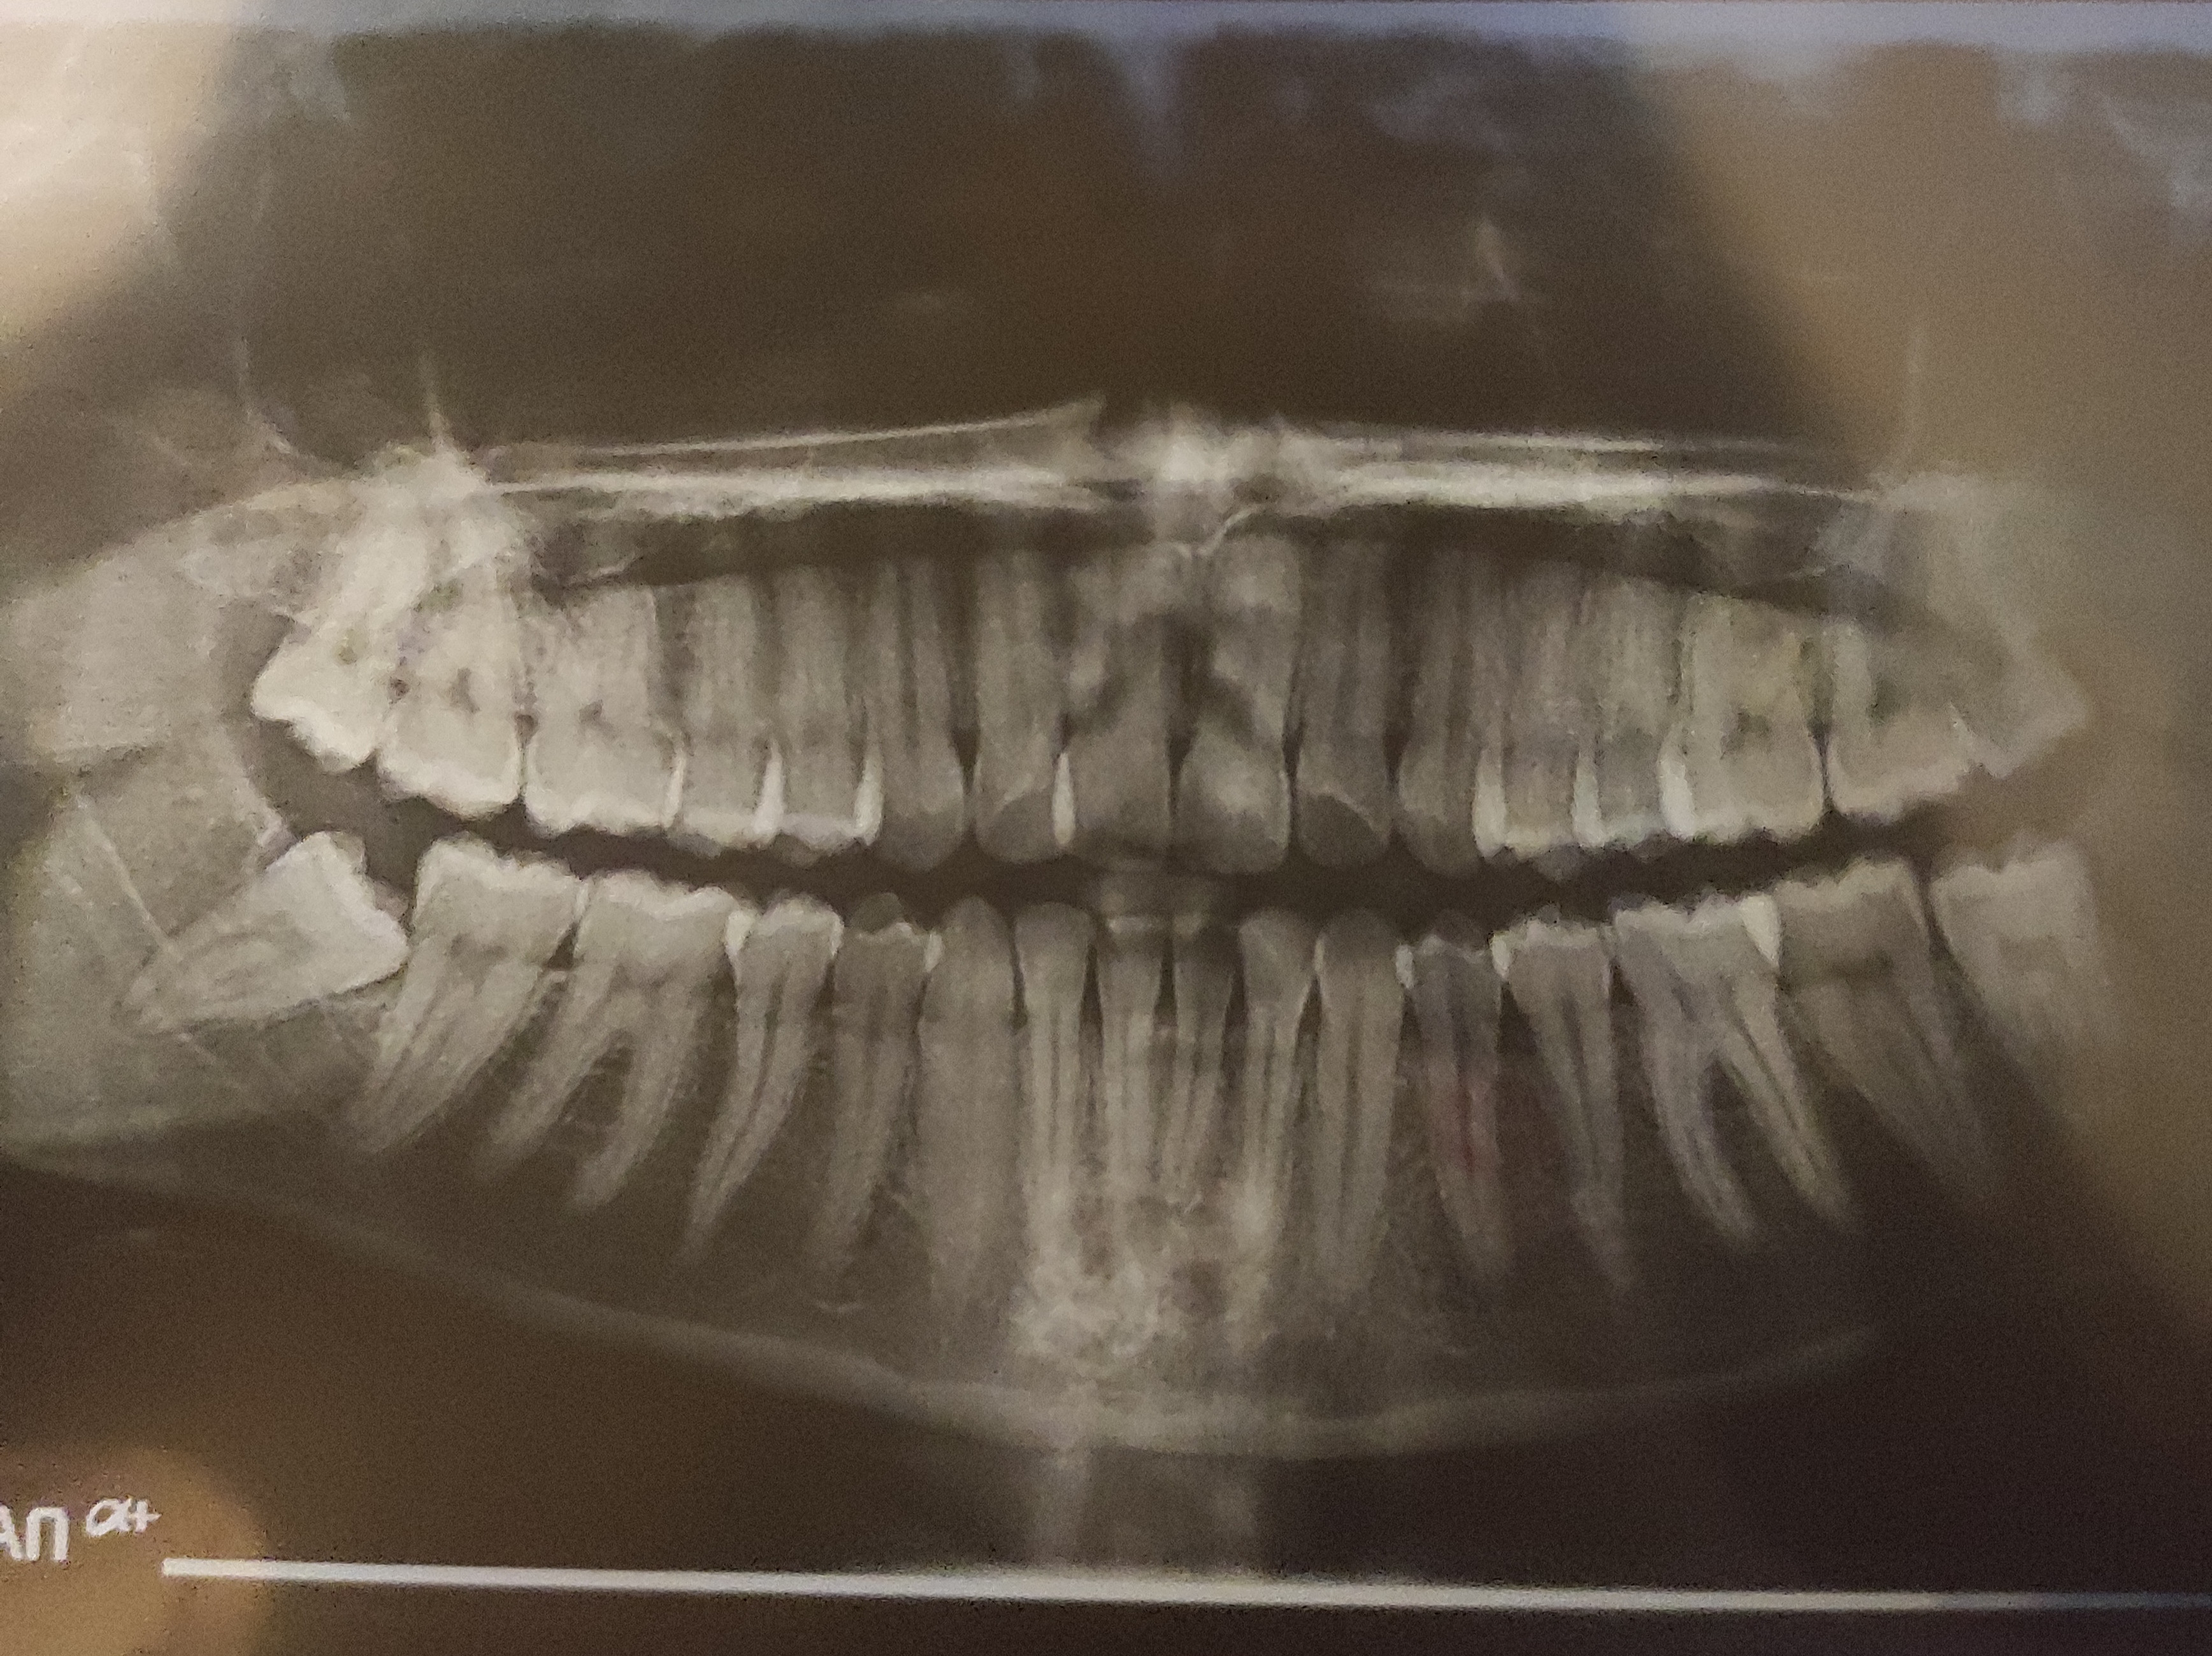

Επιτέλους πρόλαβα να βγάλω πανοραμική. Ο φρονιμίτης βγαίνει ΆΘΛΙΑ.

Μπορεί κάποιος να καταλάβει αν έχει κάνει ζημιά τελικά;

Δεν φαίνεται να έχει προκαλέσει προβλήματα στο διπλανό δόντι αλλά είναι θέμα χρόνου να το κάνει. Δεν θα προκαλέσει προβλήματα αύριο αλλά μη το αφήσεις και μήνες.Επιτέλους πρόλαβα να βγάλω πανοραμική. Ο φρονιμίτης βγαίνει ΆΘΛΙΑ.